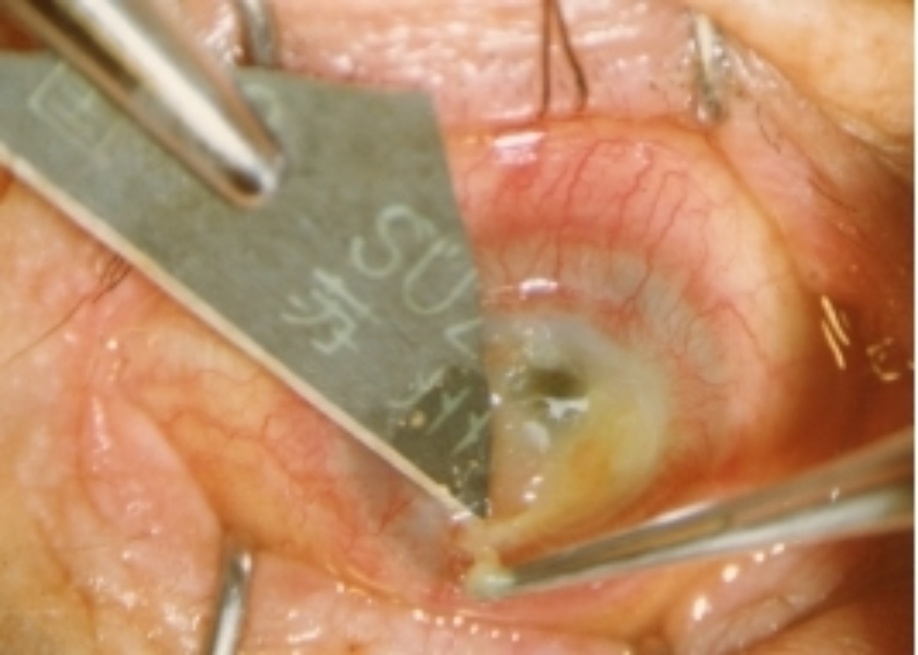

3.2. 手术方法和术后处理

在手术显微镜下(或用手术扩大镜),彻底切除病变组织,做好植床,用划界的环钻钻取全层鹅角膜后刮掉内皮层,或用角膜剪剪取整个鹅角膜刮掉内皮层。再按切除病变后植床的形状和大小做成鹅角膜移植片,用9个0单丝尼龙线间断加连续缝合固定移植片。结膜下注入庆大霉素和氟美松,压迫绷带包扎一周。每天更换敷料,涂1%阿托品眼膏和四环素可的松眼膏。口服地塞米松,一周拆除间断缝线,1~2个月拆除连续缝线。

附 录

鹅角膜板层移植部分病例

第二例